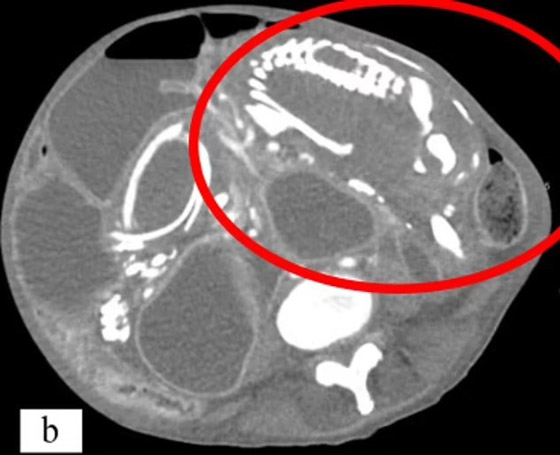

توفيت امرأة بسبب سوء التغذية الحاد بعد أن حملت جنيناً لم يولد بعد قرابة تسع سنوات داخل جسدها. وزارت المرأة، وهي في الأصل من الكونغو الأطباء في نيويورك وهي تشكو من تقلصات في المعدة وعسر الهضم وصوت غرغرة بعد تناول الطعام. وكشفت الفحوصات أن المرأة البالغة من العمر 50 عاماً لديها جنين متكلس ضغط على أمعائها، والذي يُعزى إلى إجهاض حدث قبل تسع سنوات.

الظاهرة النادرة، التي تم تسجيلها أقل من 300 مرة فقط، تحدث عندما يموت الجنين الذي ينمو خارج الرحم أثناء الحمل ولا يتم إطلاقه من الجسم. وهو من بين العديد من مضاعفات الحمل التي لها آثار طويلة الأمد على صحة الأم. ورفضت المريضة العلاج، قائلة إنها تعتقد أن حالتها الصحية مرتبطة بـ "تعويذة" ألقاها عليها شخص ما في إفريقيا. وتوفيت المرأة بعد 14 شهراً من وصولها إلى الولايات المتحدة. وقال الأطباء إنها ماتت من سوء التغذية الحاد أو الجوع.

وفي هذه الحالات، قد يكون سبب الوفاة في نهاية المطاف هو تدهور الأنسجة مما يؤدي إلى السكتة القلبية أو عدم انتظام ضربات القلب، وعدم انتظام ضربات القلب. وتشمل الأسباب الأخرى العدوى الناتجة عن ضعف جهاز المناعة. وبالنسبة لهذه المرأة، ظل "الطفل المتحجر" يضغط على الأمعاء. وتسبب هذا في انسداد أمعائها، مما يعني أن جسدها لم يعد قادراً على امتصاص العناصر الغذائية الحيوية. وقال الدكتور وسيم سوس، خبير الطب الباطني في جامعة ولاية نيويورك الطبية التي أبلغت عن الحالة، إن المريضة "رفضت التدخل خوفاً من الجراحة، ولسوء الحظ، توفيت بسبب سوء التغذية الحاد في سياق انسداد الأمعاء المتكرر والخوف المستمر من طلب الرعاية الطبية".

ولم يستطع الأطباء تحديد مكان حدوث الحمل في الجسم، لكنهم خلصوا إلى أنه من المحتمل أن يكون خارج الرحم. وعندما يموت الطفل، يكون حجمه أكبر من أن يمتصه الجسم مرة أخرى. ونتيجة لذلك، يقرر الجهاز المناعي أن الجنين الميت يشكل تهديداً للجسم. ويؤدي هذا إلى ترسب رواسب غنية بالكالسيوم على الجنين، وتغليفه تدريجياً بقشرة متكلسة أو تحويله إلى حجر. وتوقف الجنين - الذي كان من الممكن أن يكون الطفل التاسع للمرأة - عن النمو بداخلها في الأسبوع 28. لكن بدلاً من الإجهاض، عانت من الحالة المعروفة باسم lithopedion. وتحدث الحالة عندما يتكون الحمل في البطن بدلاً من الرحم. وفي هذه الحالة لا تصل كمية كافية من الدم إلى الطفل، مما يؤدي إلى فشل الحمل. ولا يستطيع الجسم طرد الجنين أيضاً، مما يؤدي إلى مضاعفات مميتة.